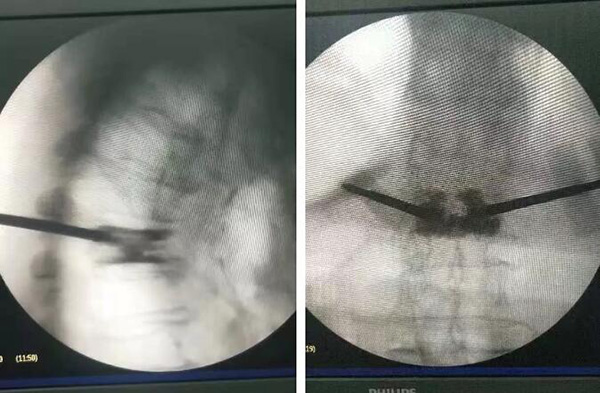

10月29日手術(shù)現(xiàn)場

廣安醫(yī)院脊柱科戈才華主任親自主刀,在局部麻醉的情況下,為陳爺爺實施了“胸7/腰1椎體壓縮性骨折經(jīng)經(jīng)皮穿刺球囊擴(kuò)張椎體成形術(shù)。”